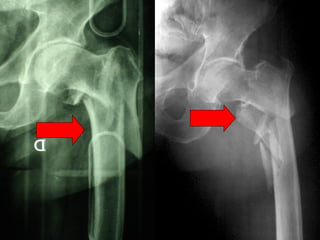

Tradizionalmente si ritiene importante per la stabilità delle fratture pertrocanteriche l’integrità della parte mediale della metafisi prossimale del femore

In realtà la zona più importante per la ricostruzione di questo tipo di fratture è il muro laterale contro il quale si impatta il frammento metaepifisario mediale

Se il muro laterale è rotto o viene lesionato durante la sintesi , come spesso accade in fase di applicazione della vite cefalica dei chiodi endomidollari o della vite-placca, andremo incontro al collasso della frattura e ad un conseguente lungo periodo di impotenza funzionale

CONCLUSIONI Perché non mettere un chiodo?  Senz’altro se il muro  laterale è fratturato  così come il punto di introduzione della  vite cefalica,perché la tecnica è più semplice

… ma  se il muro laterale è integro , la sintesi con la placca di Gotfried è  migliore e se  applicata con la  necessaria perizia tecnica garantisce  ottimi risultati.